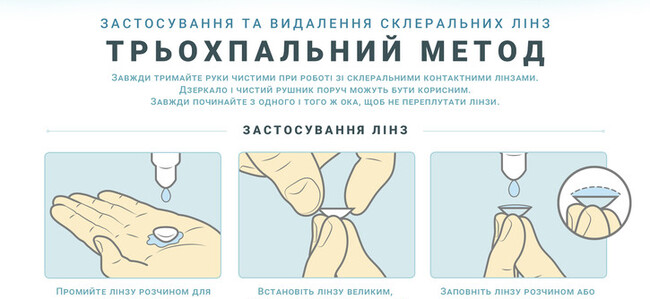

Застосування та видалення склеральних лінз